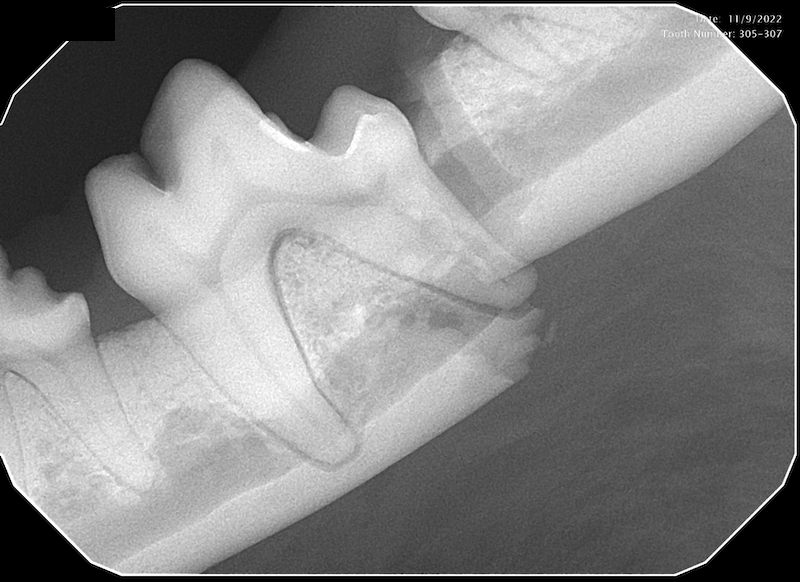

With the advent of readily available intra-oral dental radiographs, veterinarians have been able to diagnose and treat problems that had previously gone undetected.

While dental radiographs are important, we are pleased to announce that we will be offering Cone Beam Computed Tomography (CBCT). Our state-of-the-art Germantown clinic has the capability to take three-dimensional images of your pet’s mouth and teeth. This will allow even more accurate diagnosis and improve patient treatment planning.